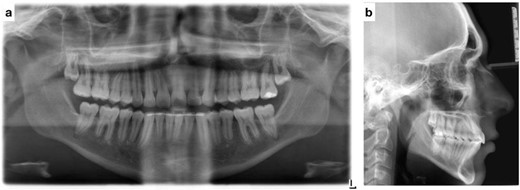

Post-treatment clinical examination showed that crowding was relieved by a 4-mm increase in the intermolar width of the maxillary and mandibular arches. In addition, a class I molar and canine relationship was achieved with good occlusion (Fig. 5) and a pleasing smile (Fig. 6). Post-treatment lateral cephalometric radiographs showed that the mandible had grown forward in the sagittal dimension, improving the skeletal profile (Fig. 7b). The upper incisors were proclined by 15° to achieve ideal labio-lingual inclination for optimum aesthetics; the lower incisor was optimally positioned to achieve ideal overjet and overbite (Fig. 7b). Mandibular anterior teeth were intruded to correct the impinging overbite and level the Curve of Spee. Finally, the patient was referred to an oral surgeon for extraction of the third molars.

(a) Post-treatment panoramic radiograph; (b) post-treatment lateral cephalometric radiograph